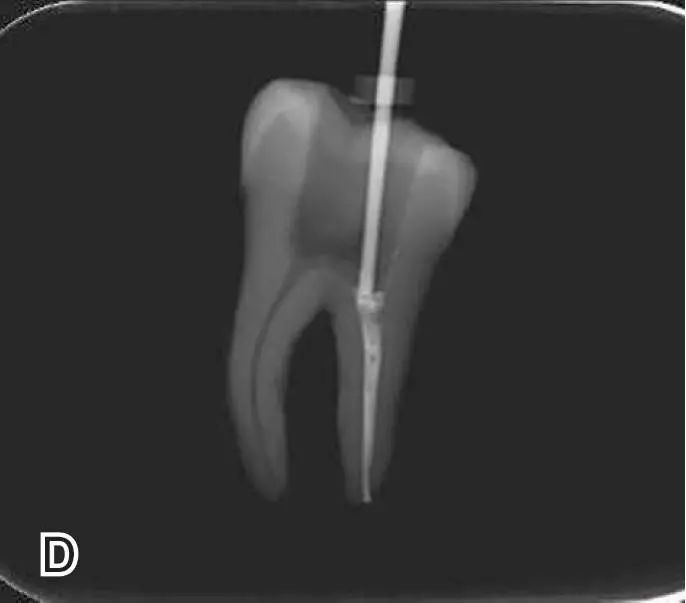

退出携热器工作尖

开启加热器1秒钟,迅速退出携热器工作尖,带出中上段多余牙胶尖。用小号垂直加压器向下加压,完成根尖段的充填。

热牙胶根中上段的充填

在完成根尖段的充填后,使用热塑牙胶注射仪对根管中上段进行分层充填,一般分2~3次完成充填,每次充填均使用相应直径大小的垂直加压器进行加压。拍片确认充填效果。